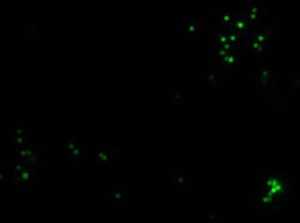

Микроскопическая оценка фагоцитоза латексных частиц

Микроскопия в проходящем свете, 100×

Флуоресцентная микроскопия, 100× (поглощение - 495 нм, эмиссия - 517 нм)